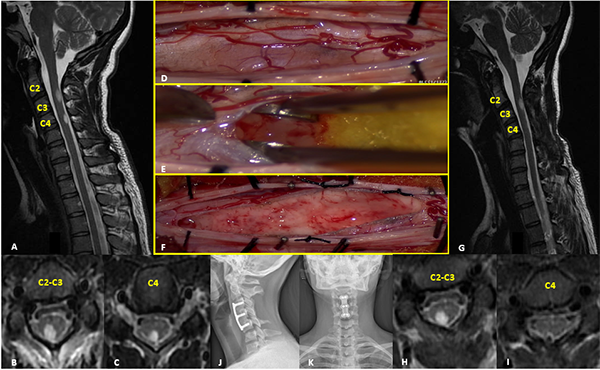

Paciente sexo femenino de 7 años sin antecedentes patológicos de relevancia que consulta por escoliosis y disestesias en miembros inferiores de 6 meses de evolución. Examen neurológico sin déficits motor. En la RM se objetiva extensa lesión intramedular de aspecto infiltrante y bordes poco precisos, extendiéndose desde la unión cérvico-dorsal al nivel D11, predominantemente hipointensa en T1 e hiperintensa en T2, con área de realce anular de aspecto quístico-necrótico a nivel D7. PESS alterados en miembro inferior izquierdo. Se realizó exéresis total de la lesión. El monitoreo neurofisiológico intraoperatorio evidenció episodios de disminución transitoria de la amplitud de la onda D, que revirtieron al detener la exéresis de la lesión. Los PEM no mostraron variaciones significativas. Presentó una paraparesia severa postoperatoria que mejoró progresivamente con rehabilitación. RM control postoperatoria evidencia resección tumoral completa con desplazamiento de lámina de D2 que requirió corrección quirúrgica. La anatomía patológica reveló ependimoma con diferenciación tanicítica focal y células claras. Actualmente sin recurrencia tumoral, en seguimiento estrecho por progresión de escoliosis (Figura 1).

Figura 1:

Ependimoma. A-D: RM prequirúrgica T1 con contraste y T2 cortes axiales y sagitales. E-F: Imágenes intraoperatoria pre y postresección. G-J: RM postquirúrgica T1 con contraste y T2 cortes axiales y sagitales.